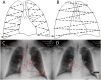

Radiologists rely principally on visual inspection to detect, describe, and classify findings in medical images. As most interpretive errors in radiology are perceptual in nature, understanding the path to radiologic expertise during image analysis is essential to educate future generations of radiologists. We review the perceptual tasks and challenges in radiologic diagnosis, discuss models of radiologic image perception, consider the application of perceptual learning methods in medical training, and suggest a new approach to understanding perceptional expertise. Specific principled enhancements to educational practices in radiology promise to deepen perceptual expertise among radiologists with the goal of improving training and reducing medical error.